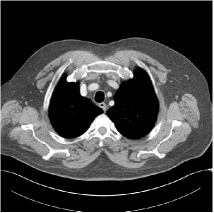

Fig. 3: Three examples (from top to bottom) of the reconstructed testing images using Momentum-Net with SimpleCNN (the second column), with SimpleCNN-RSN (the third column), and with Dn-RSN (the fourth column). The compared WavResNet denoised images are shown in the first column, and the reference images are in the fifth column. See their FBP images in Fig. 4.

Refer to caption

Fig. 4: FBP images of test examples.

3.2 Proposed Momentum-Net with SimpleCNN

Fig. 2 shows that the proposed Momentum-Net with SimpleCNN decreases RMSE dramatically in the first 30 layers, and tends to converge in 50 layers. The Momentum-Net reduces the mean RMSE value by 4.5 HU and gives smaller standard deviations in RMSE, compared to WavResNet, as reported in Table 1. This implies that the proposed Momentum-Net with SimpleCNN can improve both the accuracy and stability of low-dose CT image reconstruction than a state-of-the-art image denoising deep NN, WavResNet. The proposed Momentum-Net with SimpleCNN better removes noise and streak artifacts than WavResNet. It also provides clearer reconstructions of some details; see, in Fig. 3, the boundaries shown in the zoomed region at the top-right corner in the first example, the arrow pointed structures in zoomed areas of the second example, and the arrow pointed tissues in the left zoomed region in the third example.

3.3 Momentum-Nets involving RSN-based training

We show the reconstructed examples by Momentum-Net with SimpleCNN-RSN and Dn-RSN in the third and fourth columns of Fig. 3 respectively. Comparing the first three and the last columns in Fig. 3, we observe that Momentum-Net with SimpleCNN-RSN provides generally noisier reconstructions than WavResNet and Momentum-Net with SimpleCNN. However, Momentum-Net with SimpleCNN-RSN sometimes can provide clearer details than WavResNet. For example, in the right zoomed box of the second example, Momentum-Net with SimpleCNN-RSN shows better reconstruction quality for the arrow pointed structures than WavResNet, and in the left zoomed box in the third row, the former gives clearer small tissues marked by red arrows than the latter. Table 1 reports that Momentum-Net with SimpleCNN-RSN is approximately 2.9 RMSE (HU) higher than WavResNet, while it has smaller standard deviations. This implies that Momentum-Net with SimpleCNN-RSN is more stable than WavResNet, although it may not provide better image qualities. Momentum-Net with Dn-RSN, however, provides the worst visual and numerical results among the compared four methods in this paper.